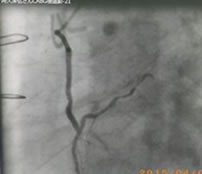

下の写真は、冠動脈バイパス術後の造影です。すでに手術から数日経った退院前の造影検査です。我々心臓外科医にとっては、循環器内科医師の先生からの「試験」を受けているようなモノです。ここで良い評価が得られないと、内科からの手術適用患者の紹介が途絶えることになります。

目安となる一つは、「グラフト開存率」です。バイパスに用いた代用の血管を「グラフト」と言い、術後にグラフトが狭窄や閉塞を起こさずに機能し続ける割合を言います。毎年、年末にこのグラフト開存率を計算します。これが落ちてきたら、その術医には患者さんが紹介されなくなります。手術死亡率とグラフトか依存率が冠動脈外科医の生命線です。

私のグラフト開存率は最後まで 95%以上だったので、心臓外科医としては良しとしていただきましょう。

図5:橈骨動脈をグラフトとして左前下行枝に吻合した例